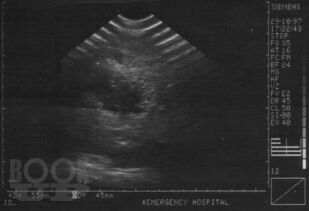

Ультразвуковая диагностика при закрытой травме органов брюшной полости и забрюшинного пространства

В монографии изложены основные достижения в диагностике закрытой травмы живота, приведены методики УЗИ с описанием эхосемиотики повреждений различных органов брюшной полости и забрюшинного пространства. Включены клинические примеры и большой иллюстративный материал, полученные в процессе собственных исследований. Приведен и аргументирован разработанный на кафедре госпитальной хирургии ВолгГМУ алгоритм диагностики и лечения сочетанной закрытой травмы живота, что определяет выраженную практическую направленность данной рукописи. Монография представляется весьма ценной для студентов старших курсов лечебных факультетов медицинских вузов, клинических ординаторов, практических врачей.